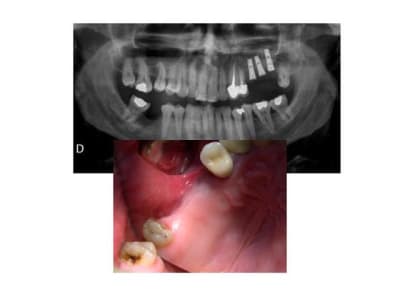

voilà, pour revenir à ce qu'on disait: une petite illustration: 25 et 27 ont été extraites. et voici la suite.

Pano initiale rhx4jg - Eugenol

Initial rir4cj - Eugenol

et la suite

Décollement membrane ljuoee - Eugenol

Implants iwsvxa - Eugenol